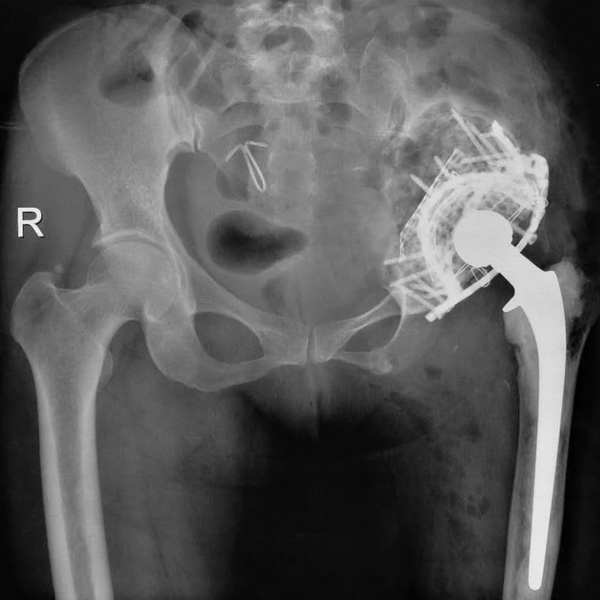

• 先天性髖關節脫位先天性髖關節脫位手術后手術前

先天性髖關節脫位

患者王某某,女,41歲,從會走路以來就發現一條腿長,一條腿短,也就是人們俗稱的“跛子”,之前雖然兩條腿長短不一,但起碼還可以走路,維......

在線咨詢+更多詳情+